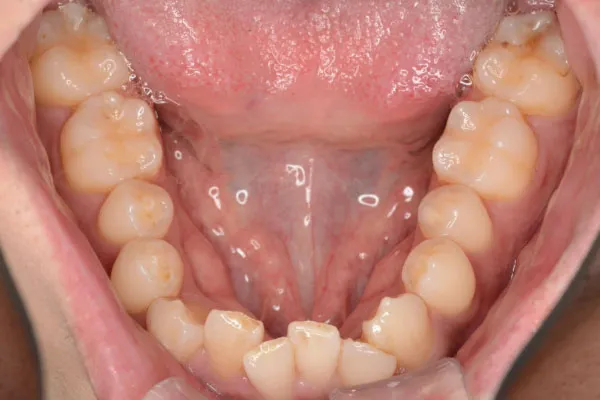

【30代男性】

下の歯のガタつきを

インビザライン矯正で

治療したケース

治療前

| 主訴 | 下の歯のガタつきが気になる |

|---|---|

| 期間 | 2年 |

| 費用 | 220,000円〜660,000円 (デンタルローン 3,100〜6,600円/月) |

| 治療内容 | インザライン矯正 非抜歯 |

| 治療に伴うリスク | 矯正終了後は、リテーナーを指示通りに使用し、歯の後戻りを防ぐ必要があります。 |